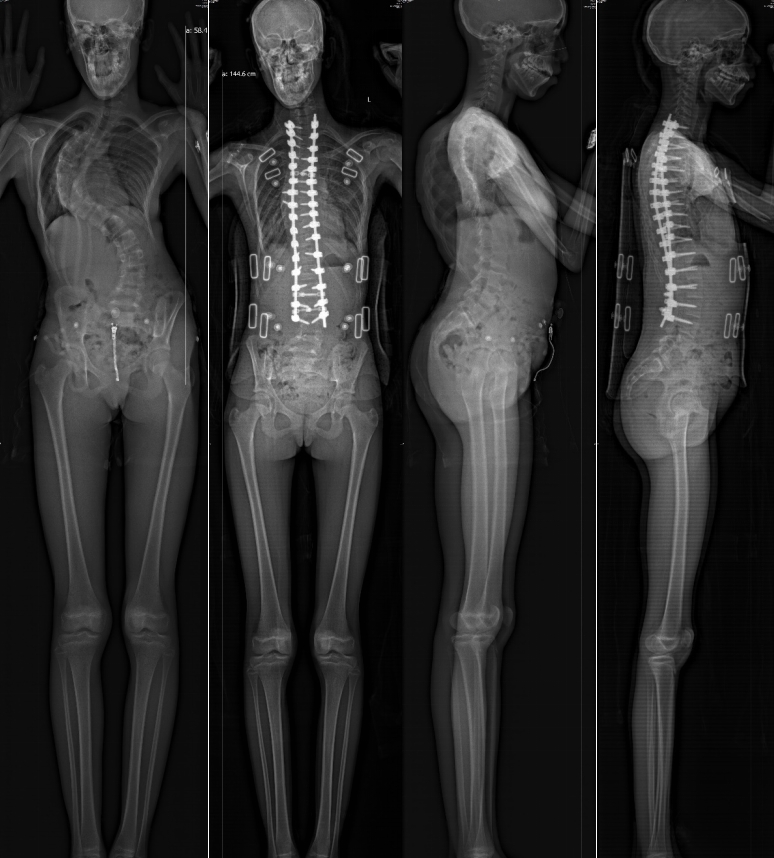

A 12-year-old girl from the UK, also known as Little D, is recovering well after undergoing complex corrective surgery for severe scoliosis in Shanghai last month. Once facing the prospect of never standing straight, she now shows promising signs of recovery.

Her condition, marked by a 104-degree spinal curvature, had worsened rapidly despite bracing, prompting her family to seek specialized treatment in China.

​Images demonstrate the difference in patient Little D's condition before and after surgery. [Photo/Xinhua Hospital]

Her case was particularly complex due to the severity of her spinal deformity, significant razorback deformity, and restrictive respiratory dysfunction.

The four-hour operation, completed in July, involved osteotomy and derotation techniques to correct the severe spinal curvature while preserving as much spinal flexibility as possible.

Surgeons limited the spinal fusion to L4, preserving 20 percent more bending function compared to traditional fusion at L5. The team achieved nearly 80 percent correction of the scoliosis.

Following the procedure, Little D grew eight centimeters taller and regained the ability to walk, bend, and climb stairs within a week.